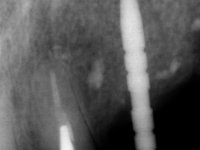

66-year-old male patient, non-smoker. It featured a 5-member metal-ceramic bridge with extreme mobility. Teeth 11 and 21 had infiltrated cervical margins. Both arches showed root exposure with signs of cervical abrasion. Composite resin “slots” were visible on the buccal surfaces of some mandibular teeth compatible with an orthodontic treatment with aligners that the patient was undergoing. After the imaging examination, it was found that the bridge's distal support, tooth 24, was irretrievably lost. The mesial pillars 11 and 21 had endodontic treatment and intraradicular posts. Teeth 25 and 26 also had endodontic treatment and extensive restorations in composite resin. In the lower jaw, two bridges were visible. In the third quadrant a 4-element bridge supported on tooth 35 and on 2 implants placed in the location of teeth 36 and 37. In the fourth quadrant a 3-element bridge supported on tooth 45 and an implant placed in the location of tooth 46. The patient presented a thick gingival phenotype and very good oral hygiene.

A temporary acrylic bridge made in the laboratory with 7 elements was made, with teeth 11,21, 25 and 26 as pillars. The old bridge was removed and tooth 24 was extracted. The provisional bridge after relining was cemented in the mouth. Two implants were placed in the teeth 22 and 24 and 3 months after this intervention an impression was made to make a temporary bridge screwed over the implants and cemented to the teeth. The bridge was placed in the mouth and teeth 25 and 26 were extracted. 3 months later, surgery was performed to fill the maxillary sinus and 6 months later the implant was placed in the location of tooth 26. After osseointegration of this implant, the final impression was made for the final work. The bridge over the implants was permanently screwed on and the bridge over the teeth was cemented with resin-reinforced glass ionomer cement.